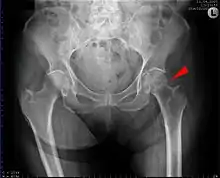

Intertrochanteric hip fracture in a 17-year-old male

A hip fracture is a break that occurs in the upper part of the femur (thigh bone).[2] Symptoms may include pain around the hip, particularly with movement, and shortening of the leg.[2] Usually the person cannot walk.[3]